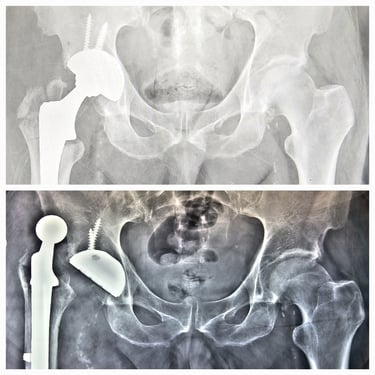

Artroplastia de cadera (prótesis total/parcial).

Cirugía de revisión de cadera y rodilla.

Manejo de secuelas y complicaciones de prótesis de cadera y rodilla.